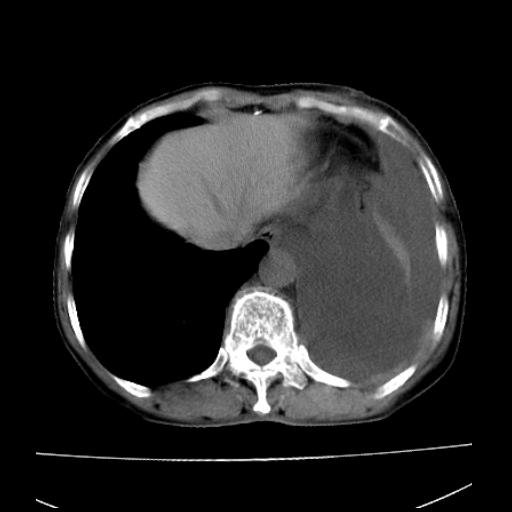

以下是引用随光逐影在2010-3-24 19:15:00的发言:[br]结合病史,考虑双肺及纵隔淋巴结多发转移、左侧胸膜转移并左侧大量胸水,左下肺膨胀不全。

以下是引用zxl51642在2010-3-24 18:49:00的发言:[br]结合乳腺癌术后病史,考虑双肺及纵隔淋巴结多发转移、左侧胸膜转移并左侧大量胸水、左下肺膨胀不全。